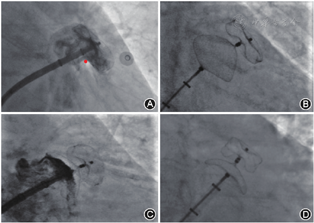

在正位X线透视下,房间隔穿刺鞘沿配套导丝送至上腔静脉,退出导丝后送入连接造影剂的穿刺针,距鞘管头端1 cm处固定,在X线透视下缓慢回撤,同时将穿刺鞘和穿刺针由12点钟方向逐渐指向5点钟左右方向的房间隔部位(根据心房大小调整方向),后前位(postero-anterior,PA)时鞘尖以位于左心房影下缘上半个至一个椎体高度为宜(图1A)。当鞘尖顶住房间隔后,在右前斜位(right anterior oblique,RAO )45°适当再次调整穿刺点至左心房后缘前半个至一个椎体为宜(图1B),以穿刺针及鞘管远段弧度消失呈直线状或接近直线状为理想穿刺点。

TTE下可观察到穿刺鞘尖端抵在房间隔上形成的"帐篷顶"现象。对于大多数患者穿刺的合适位置:(1)胸骨旁主动脉短轴切面,位于房间隔下端的中下1/3处(图1C);(2)心尖四腔心切面,位于房间隔中部(图1D)。